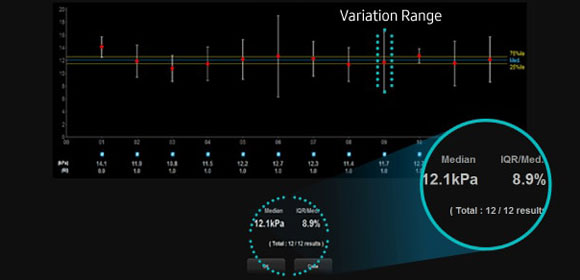

S-Shearwave

S-Shearwave este o soluție neinvazivă, care vă permite să măsurați cu ușurință rigiditatea ficatului, detectând viteza undelor care se propagă prin leziunea afectată și arătând valoarea numerică a rigidității în kPa sau m / s și un indice de fiabilitate al măsurării (* RMI). Profilul grafic oferă o gamă de variații (VR), care arată în mod intuitiv uniformitatea rigidității țesutului în zona de interes (ROI).